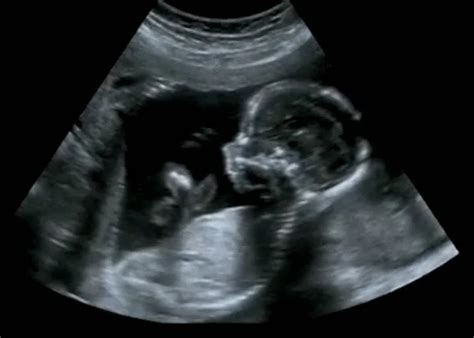

A szikhólyag és az embrió megjelenése

Az egyik legfontosabb mérőszám a CRL (ülőmagasság) lesz. Ha a petezsák mérete eléri a 20 mm-t, és még mindig nincs látható szívműködés, az a terhesség valószínűsíthető nem életképességét jelzi. Ha az embrió már látható, de nincs szívhang, és a CRL mérete meghaladja az 5-7 mm-t, ez szintén rossz prognózist jelent.

Miután a petezsákot azonosították, a következő izgalmas lépés a szikhólyag (yolk sac) megjelenése. A szikhólyag a fejlődő embrió számára létfontosságú struktúra, amely a korai hetekben ellátja a táplálkozási feladatokat, amíg a vérkeringés és a méhlepény működése el nem indul. A szikhólyag általában a terhesség 5. és 5,5. hete között válik láthatóvá, amikor a petezsák mérete eléri a 8-10 mm-t. Ha a petezsák mérete meghaladja a 10-12 mm-t, de a szikhólyag még nem látható, az szintén jelezhet fejlődési problémát.

A szikhólyag jelenléte kritikus. Azonban a mérete is számít. A túl nagy vagy túl kicsi szikhólyag is összefüggésbe hozható a terhesség rosszabb kimenetelével. Például, ha a szikhólyag átmérője meghaladja a 6 mm-t a 6. hétben, az emelheti a vetélés kockázatát.

A petezsák fejlődése a 7. hét után is folytatódik, de ekkor már más struktúrák és a magzat fejlődése kerül előtérbe. Amint a terhesség belép a 7. hétbe, a petezsák látványa már nem a fő fókusz. A petezsák mérete tovább növekszik, de a legfontosabb mérőszám a CRL (ülőmagasság) lesz.

Ha az embrió már látható, de nincs szívhang, és a CRL mérete meghaladja az 5-7 mm-t, ez szintén rossz prognózist jelent. A petezsák tehát egy rövid, de kritikus időszak jelzője. A megjelenése megerősítést, a mérete datálást, a belső tartalma pedig prognózist ad a terhesség életképességéről.